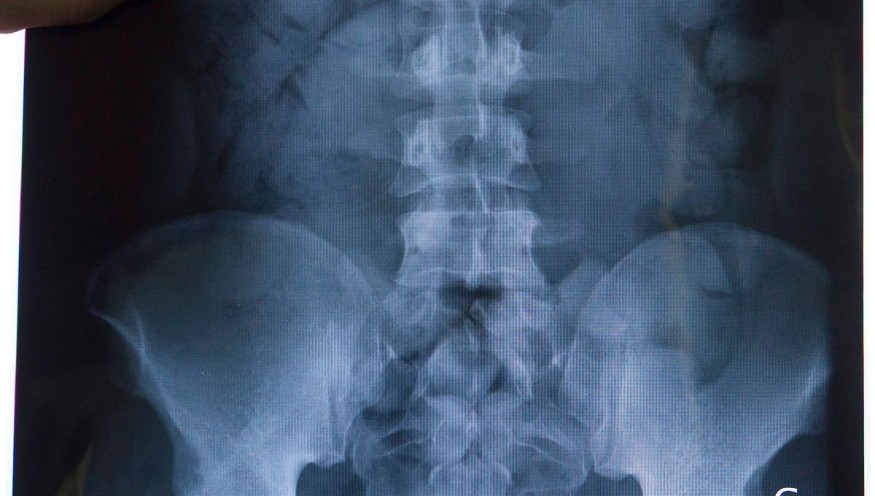

Principe de "mule" : l'individu avait avalé des ballotins pour passer les douanes, mais les services aux frontières l'attendaient. La drogue, non encore identifiée (pas de l'ice), bloquait son côlon.

Transferé au CH de Taaone, les médecins débattaient entre endoscopie et chirurgie pour extraire les paquets en grand nombre. La procureure Solène Belaouar n'a pas commenté.